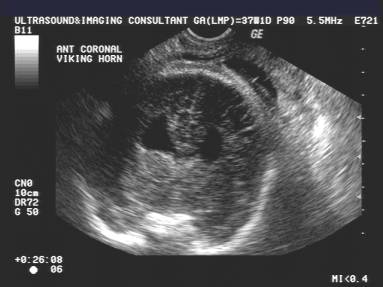

Sunburst appearance of gyri |

Normal corpus callosum, pericallosal (PC) and

callosomarginal (CM)arteries. |

Agenesis of the corpus callosum with a

"sunburst" gyral pattern and non visualization of the pericallosal

or callosomarginal arteries |